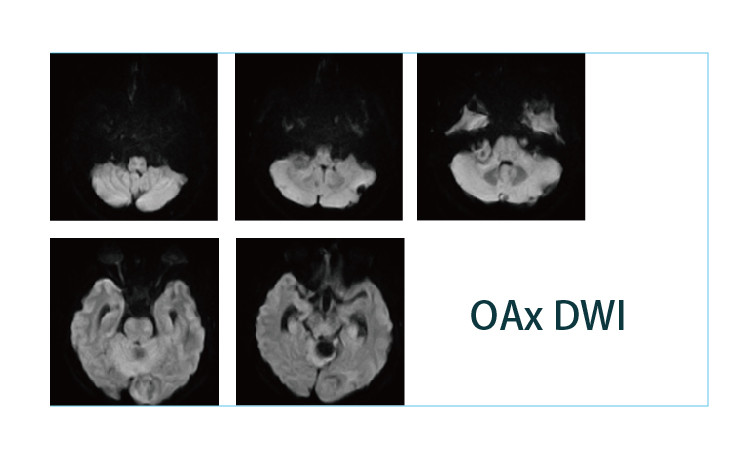

【朗润影像档案】磁共振影像病例分享(编号20190412)

2019-04-25 17:22:57